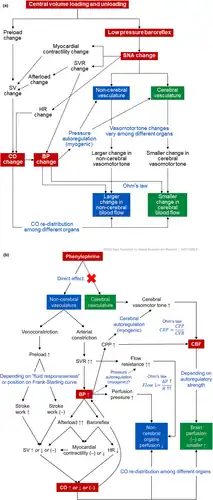

Phenylephrine is commonly used as a vasopressor to increase the blood pressure in people who are unstable with low blood pressure, especially resulting from septic shock. Such use is common in anesthesia or critical-care practices; it is especially useful in counteracting the low blood pressure effect of epidural and subarachnoid anesthetics, as well as the vasodilating effect of bacterial toxins and the inflammatory response in sepsis and systemic inflammatory response syndrome. The elimination half life of phenylephrine is about 2.5 to 3.0 hours.[16] The clinical effects of a single intravenous bolus dose of phenylephrine are short lived and may need further doses every 10–15 minutes. Commonly the drug is given as a carefully titrated intravenous infusion with a syringe pump or volumetric pump.

Heart

The primary side effect of phenylephrine is high blood pressure. People with high blood pressure are typically advised to avoid products containing it. Because this medication is a sympathomimetic amine without beta-adrenergic activity, it does not increase contractility force and output of the cardiac muscle. It may increase blood pressure resulting in a slow heart rate through stimulation of vascular (likely carotid) baroreceptors. A common side effect during IV administration is reflex bradycardia.[22] The low concentration eye drops do not cause blood pressure changes and the changes with the higher dose drops do not last long.[23]

The increase in blood pressure effect of phenylephrine may be increased by drugs such as monoamine oxidase inhibitors, tricyclic antidepressants, and hydrocortisone. Patients taking these medications may need a lower dose of phenylephrine to achieve a similar increase in blood pressure.

Drugs that may decrease the effects of phenylephrine may include calcium channel blockers, ACE inhibitors and benzodiazepines. Patients taking these medications may need a higher dose of phenylephrine to achieve a comparable increase in blood pressure.[28]

Phenylephrine is a sympathomimetic drug, which means that it mimics the actions of epinephrine (commonly known as adrenaline) or norepinephrine. Phenylephrine selectively binds to alpha-1 receptors which cause blood vessels to constrict.[21]

Whereas pseudoephedrine causes both vasoconstriction and increase of mucociliary clearance through its nonspecific adrenergic activity, phenylephrine's selective α-adrenergic agonism causes vasoconstriction alone, creating a difference in their methods of action.